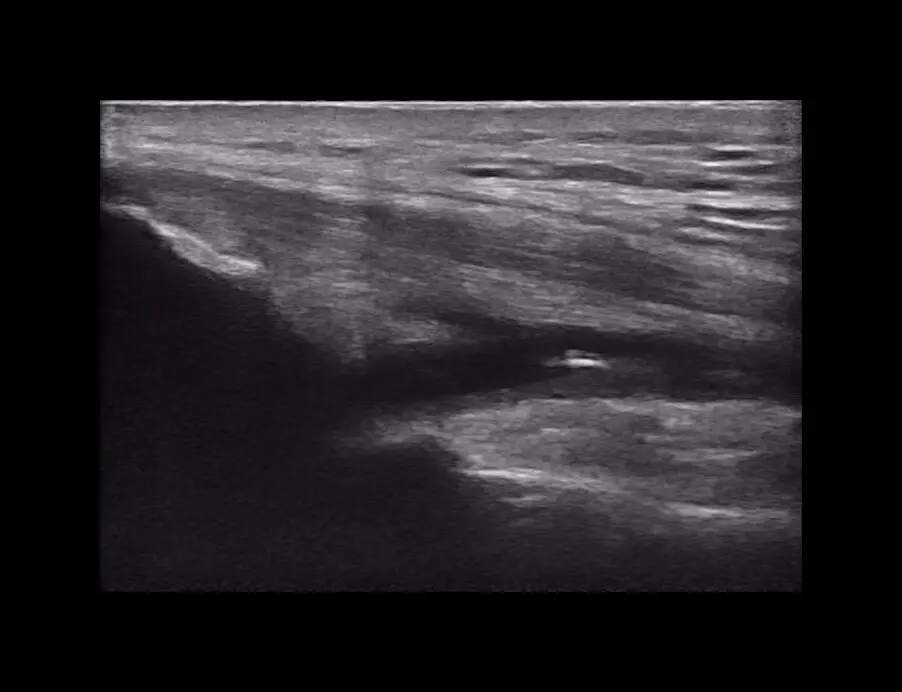

ProbeFix Dynamic is a new device that enables high-quality ultrasound measurements during dynamic exercise by keeping an ultrasound probe in place, allowing for muscle monitoring during intense movement and creating new research possibilities in muscle imaging.